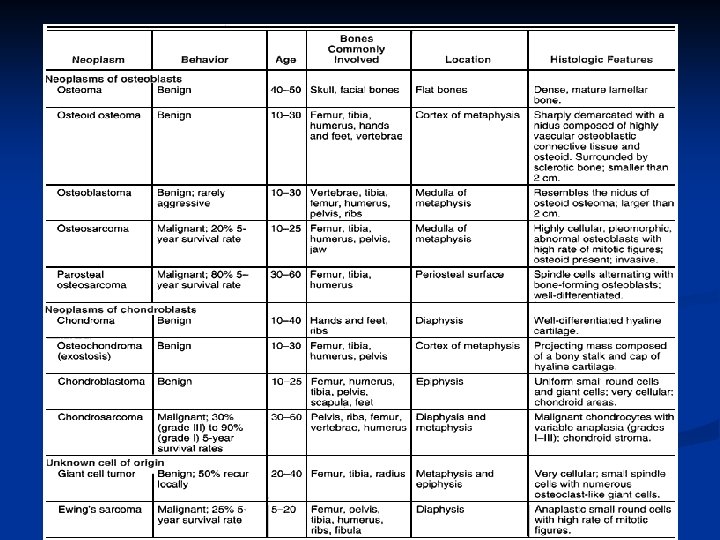

I. Cartilaginous Tumors n Osteochondroma n Solitary Enchondroma n Chondrosarcoma

Osteochondroma n n Osteocartilaginous exostosis Most common benign tumors or tumorlike lesions of bone, In almost any bone preformed in cartilage, particularly long tubular bones, Presents as a solitary cartilage-capped bony outgrowth protruding from the bone surface near the metaphysis.

Solitary Enchondroma Central Chondroma n Composed of mature hyaline cartilage n Develops in the medullary cavity of a single bone n Third to sixth decades of life n n average : between 30 and 40 years.

Chondrosarcoma A malignant cartilaginous tumor n The third to sixth decades of life (average of 45 years) n Slightly more common in males than females n

II. Bone-Forming Tumors - Osteoid Osteoma - Osteoblastoma - Osteogenic Sarcoma

Osteoblastoma n n Osteoblastomas are larger (> 2 cm) than osteoid osteomas Mainly osteolytic n n do not evoke reactive bone sclerosis Higher recurrence rate (~10%) Characterised by immature osteoid production Commonly in the cancellous bone of the spine (posterior elements) and skull

Osteogenic Sarcoma Osteosarcoma: a malignant tumor of bone n Most common primary bone tumor after myeloma n

III. Tumors of Other or Unknown Histogenesis Ewing’s sarcoma n Giant Cell Tumor n

Giant Cell Tumor An aggressive benign tumor n Composed of : n well vascularized stroma n plump, spindly, and oval tumor cells n multinucleated tumor giant cells n n Over the age of 20: most commonly in the third decade of life n slight female preponderance n